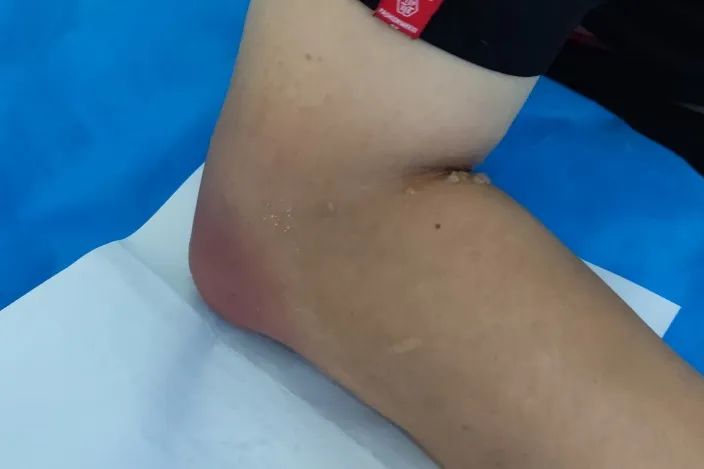

在我医院有一位痛风石患者,痛风石长满了他的双手,并且他的肘、脚上也存在一些体积较大的痛风石,来到我们医院专门为了做痛风石去除手术。这位患者心态非常轻松,认为长出来的痛风石开个刀挖出来再缝上就OK了,但是当我们和他说,他左手小指的第二节骨头已经没了,以及反复破溃的右手食指有概率保不住时,他沉默了。